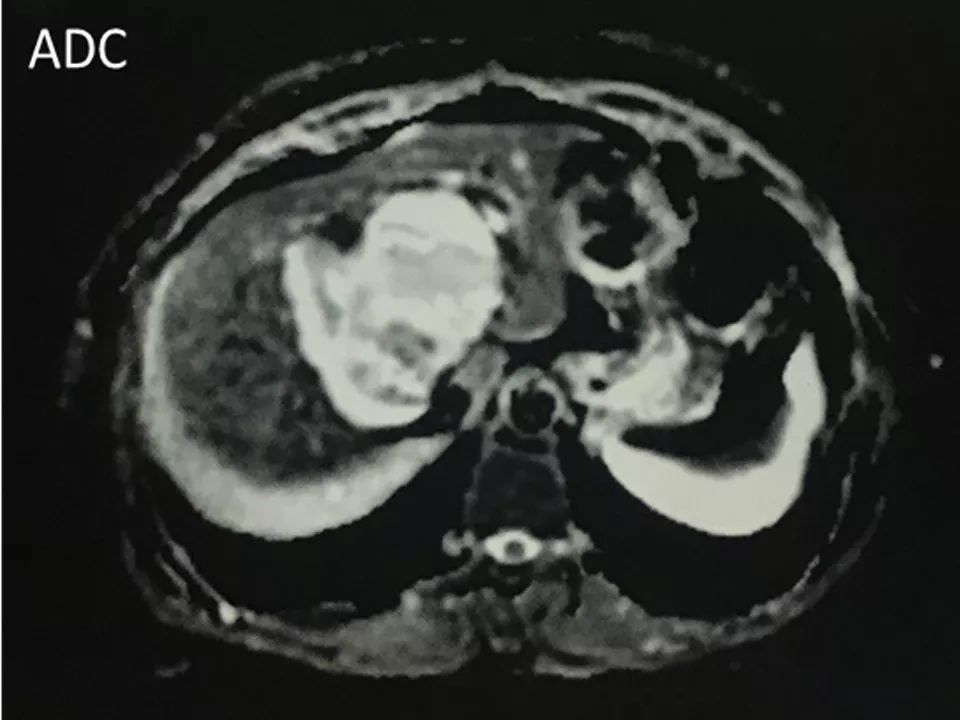

MRI表现:

肝内单发占位灶,累及肝左右叶及尾叶。T1WI示病灶以低信号为主,边缘多枚等信号结节,正反相位未见明显脂肪成份;T2WI示病灶以粘液成份为主呈高信号,边缘多枚稍高信号结节(相对肝实质),DWI呈不均匀等高信号,ADC图以高信号为主。动脉期病灶边缘均匀强化,壁结节显著强化,门脉期边缘仍持续强化,边缘光滑,壁结节呈相对等低信号。MRCP示胆管扩张,病灶与胆管相通。

影像学最重要的特点是病灶与扩张的胆管相通,病灶内见多发结节。胆管内结节T1WI呈等低信号,T2WI呈高信号,肿瘤常可分泌粘液。由于缺乏卵巢样基质,动态增强曲度呈轻度“wash-in&wash-out”,动脉晚期肿瘤呈等高信号,门脉期和延迟期呈等低信号。